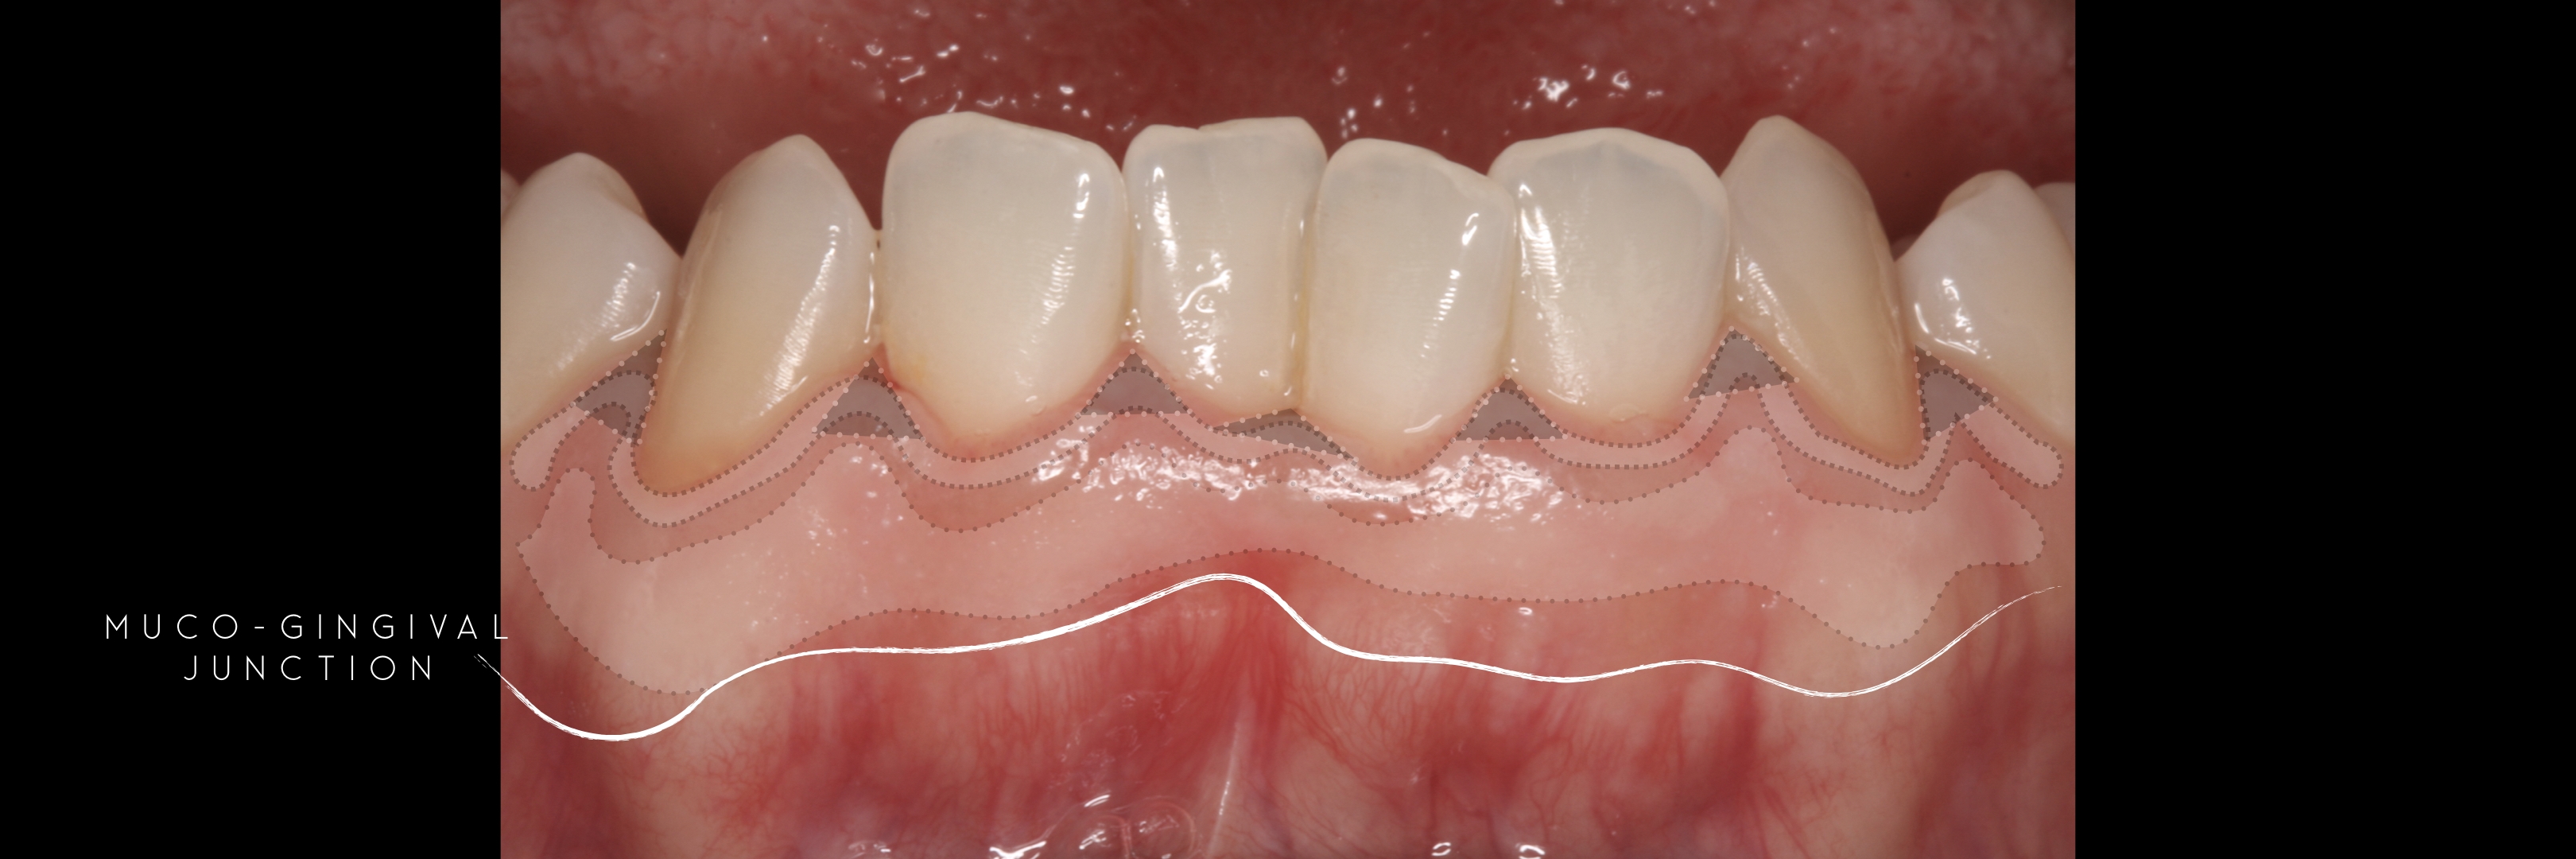

and the attached gingiva extending from the gingival mar­gin to the mucogingival junction.

Generally we tend to forget about these 2 parameters, free and the attached gingiva are both essential parts of the keratinized gingiva.

This meaning that keratinized (load bearing capacity) is a mechanical characteristic that makes up for attached gingiva, providing it's immobility,  but also is of such importance as the thickness it provides around whatever perforates the epithelium, be it implants or teeth, being also keratinized (having load bearing capacity) at this location.

The width of the keratinized gingiva may vary between 1 and 9mm.

However, the question of how much gingiva is "adequate" has still not been investigated.

There was no answer at the time of Lang and Löe's paper -1972 - and still nowadays we still lack a final answer, but attached gingiva plays a major role on stable soft tissues around teeth and implants.